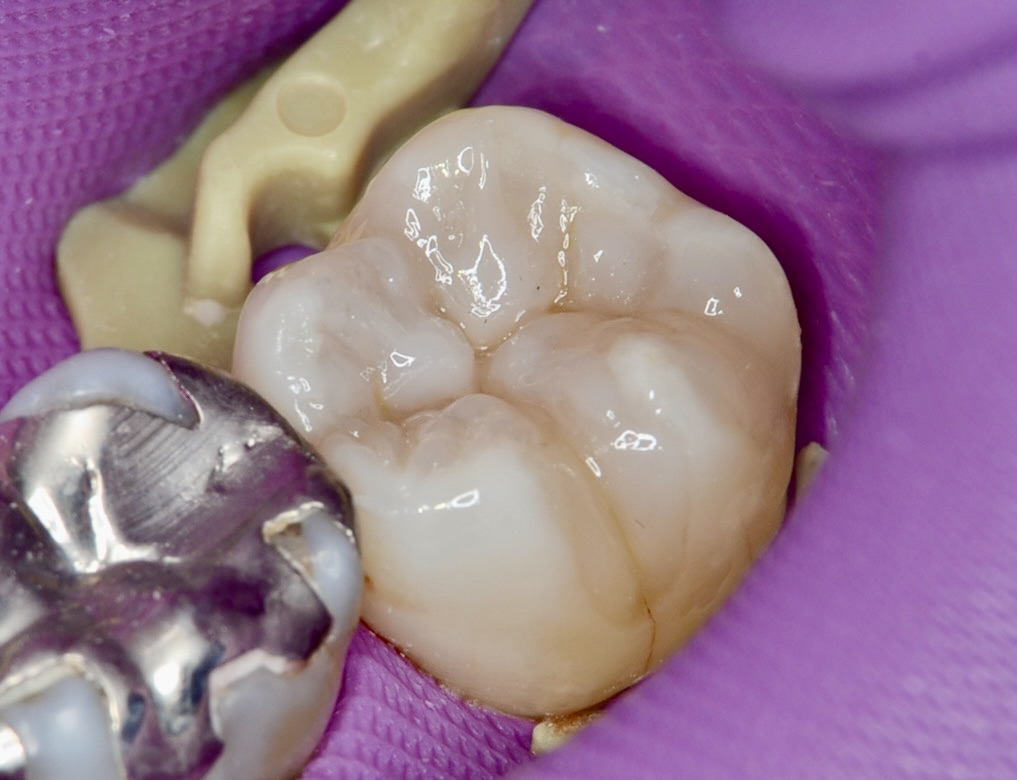

20代 虫歯治療 VPT(歯髄温存療法)ダイレクトボンディング #36

Before

After

| 年齢 | 20代 | 治療方法 | VPT(歯髄温存療法)/ダイレクトボンディング |

|---|---|---|---|

| 性別 | 女性 | 通院回数 | 2回 |

| 主訴 | むし歯を治したい /神経を取りたくない/できるだけ神経を取りたくない | 費用 | 170,500円(税込) |

| 治療のメリット | 神経を保存できる。歯を削る量を少なくできる。自然な形にできる | ||

| 治療のデメリット | 神経を保存できない場合がある。 | ||